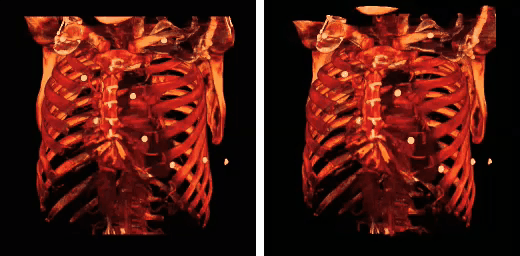

The rib cage is an arrangement of bones in the thorax of all vertebrates except the lamprey and the frog. It is formed by the vertebral column, ribs, and sternum and encloses the heart and lungs. In humans, the rib cage, also known as the thoracic cage, is a bony and cartilaginous structure which surrounds the thoracic cavity and supports the pectoral girdle (shoulder girdle), forming a core portion of the human skeleton. A typical human rib cage consists of 24 ribs, the sternum (with xiphoid process), costal cartilages, and the 12 thoracic vertebrae. Together with the skin and associated fascia and muscles, the rib cage makes up the thoracic wall and provides attachments for the muscles of the neck, thorax, upper abdomen, and back.

Rib fractures are the most common injury to the rib cage. These most frequently affect the middle ribs. When several ribs are injured, this can result in a flail chest which is a life-threatening condition.

Abnormalities of the rib cage include pectus excavatum ("sunken chest") and pectus carinatum ("pigeon chest").